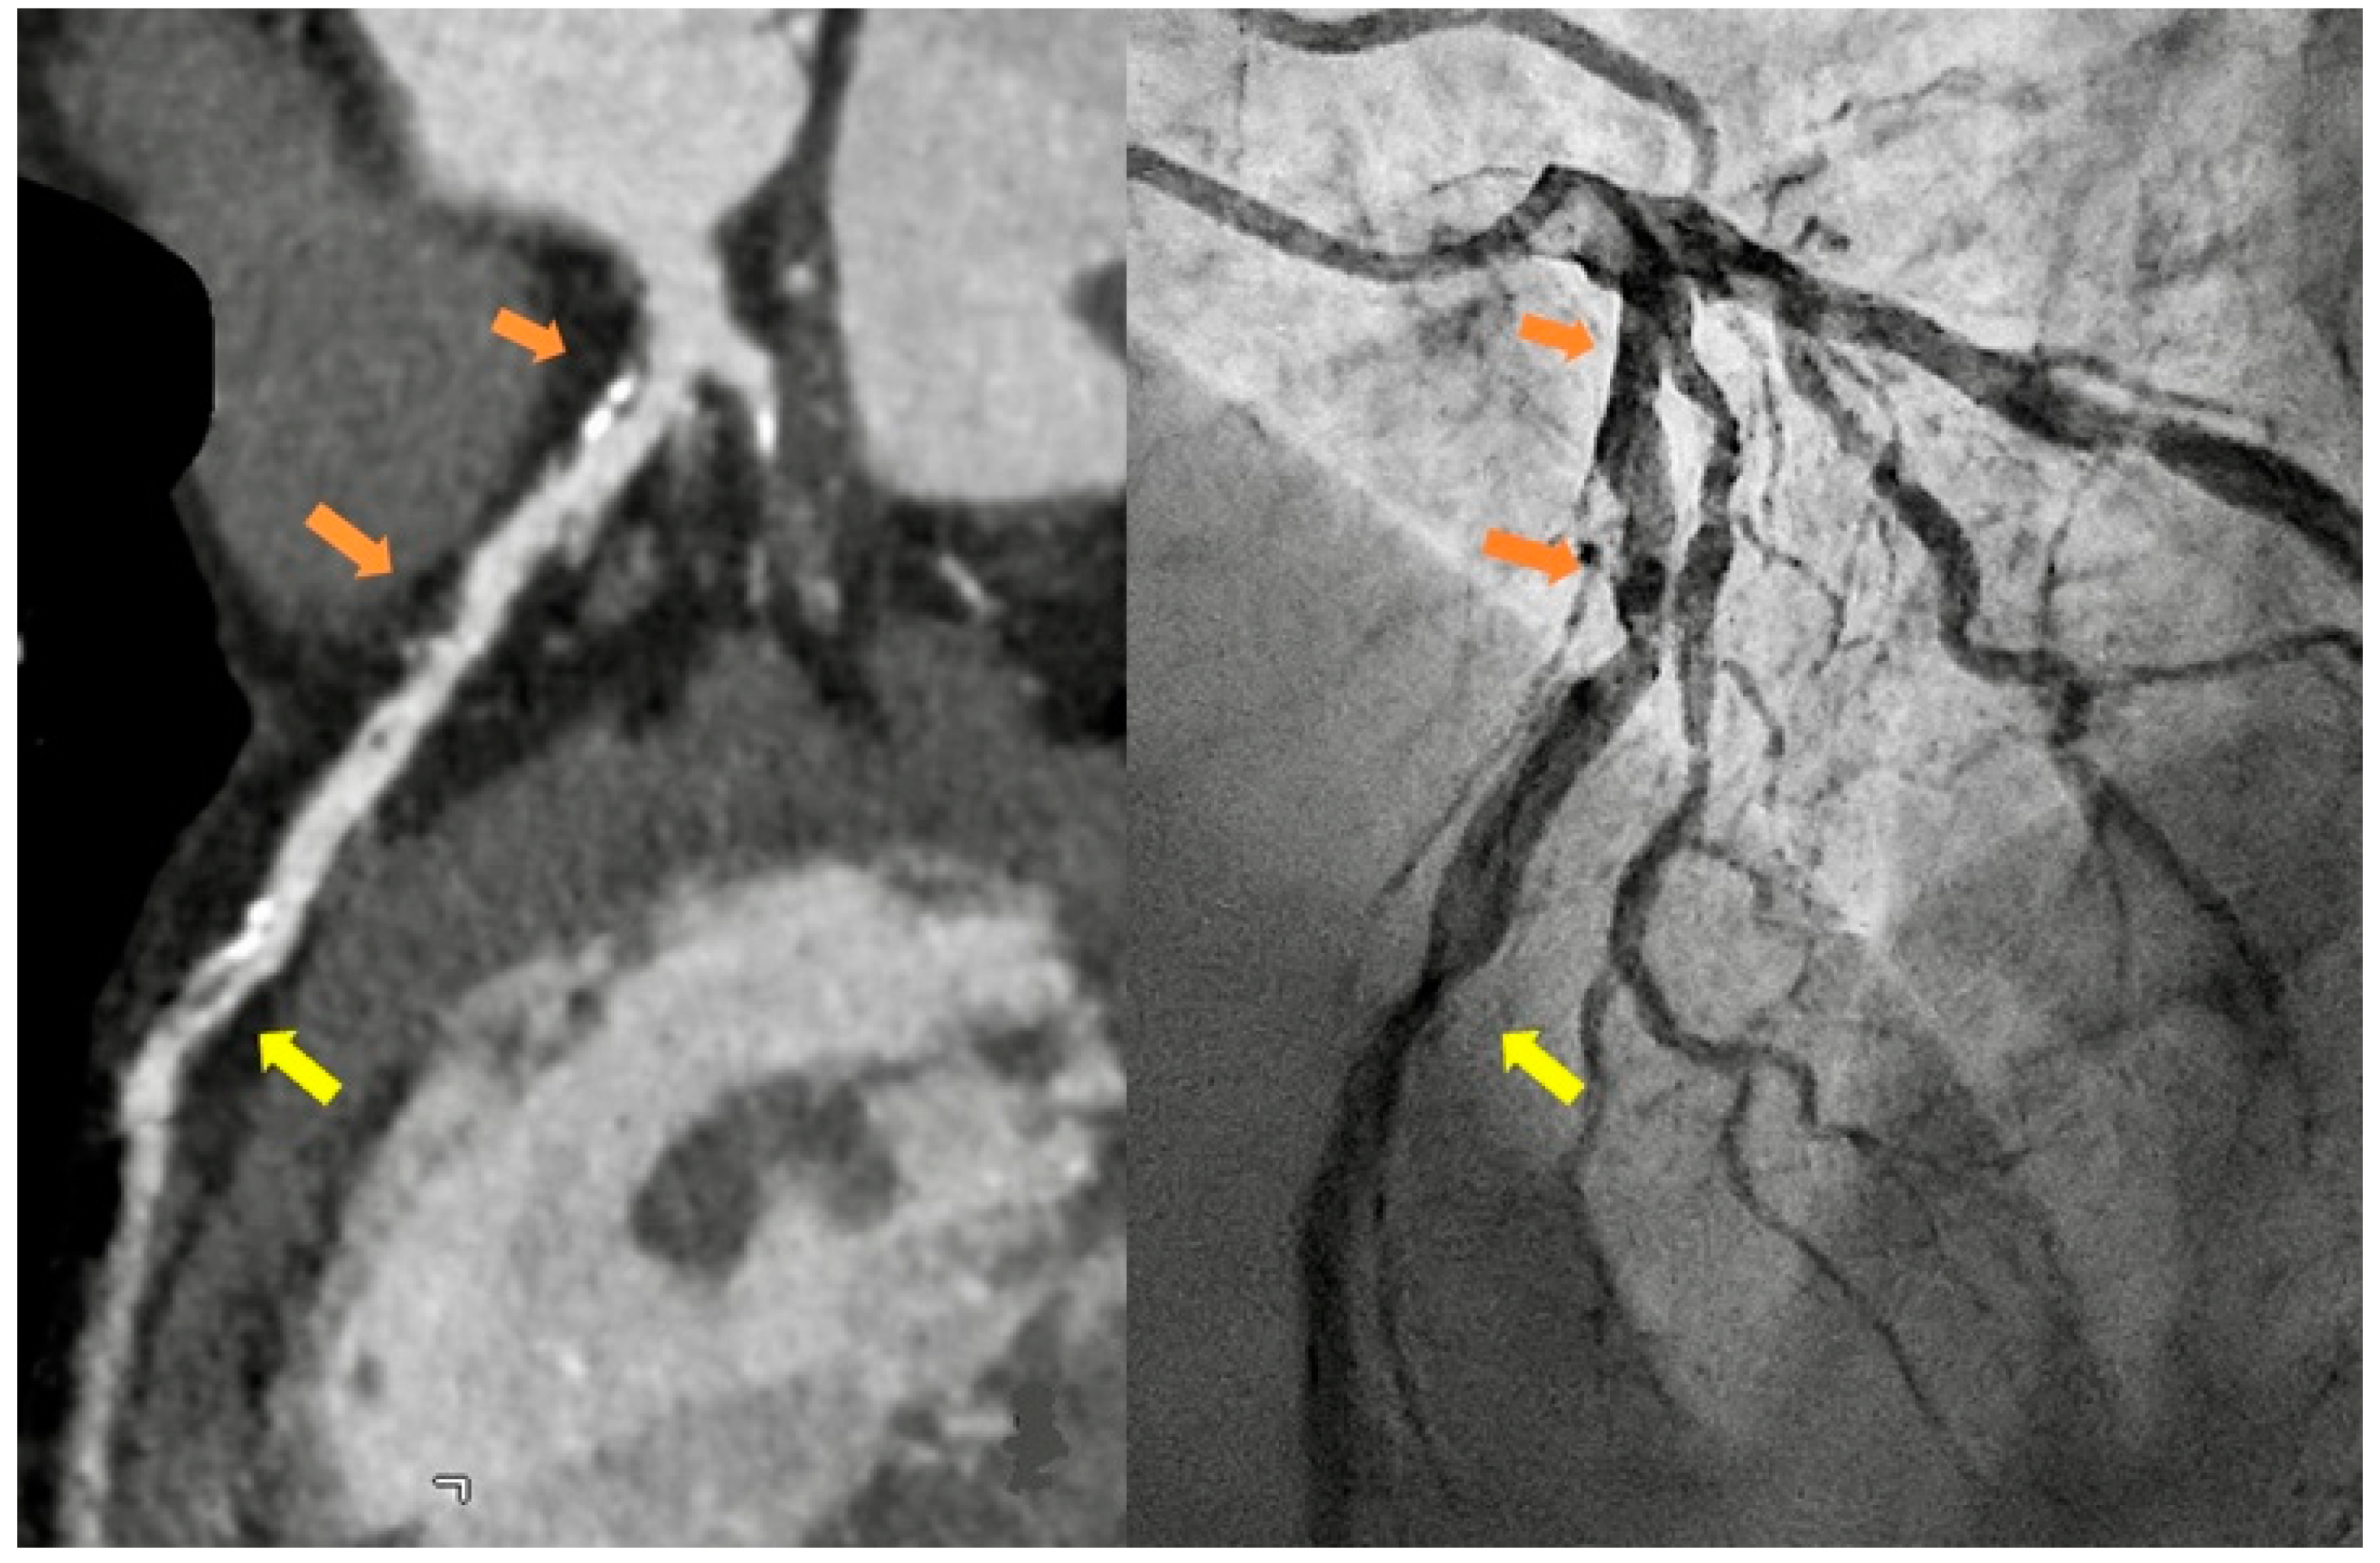

In Italy, as all over the world, the principal indications for CCT are the exclusion of obstructive CAD in symptomatic patients at intermediate clinical likelihood (class I B) with high probability for a good image quality, to improve their referral for angiography thanks to the high negative predict value of the technique, and the calcium score assessment in asymptomatic individual as a risk modifier in the cardiovascular risk assessment (class IIb B) (Knuuti et al., 2020) [Figure 1].

In the setting of the emergency room, the request for urgent CCT in patients with acute chest pain is showing a growing trend [Figure 2] and more and more hospitals have machines and personnel skilled to perform the “CT triple rule out protocol” for obstructive CAD, aortic dissection, and pulmonary embolism.